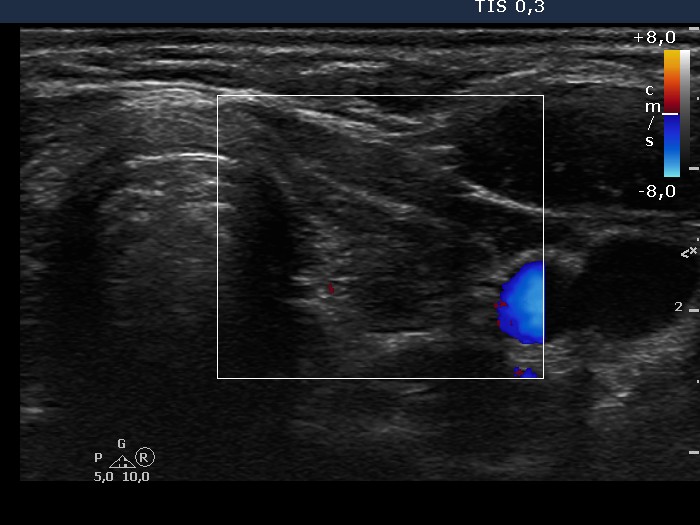

Clinical data: a 35-year-old woman with hypothyroidism replaced with 100 ug levo-tiroxin was referred for evaluation of thyroid nodules.

Functional state: euthyroidism.

Ultrasonography: there were several circumscribed areas which in fact did not fit nodules. These are active foci of autoimmune thyroiditis.

Cytological report: benign Hashimoto's thyroiditis.